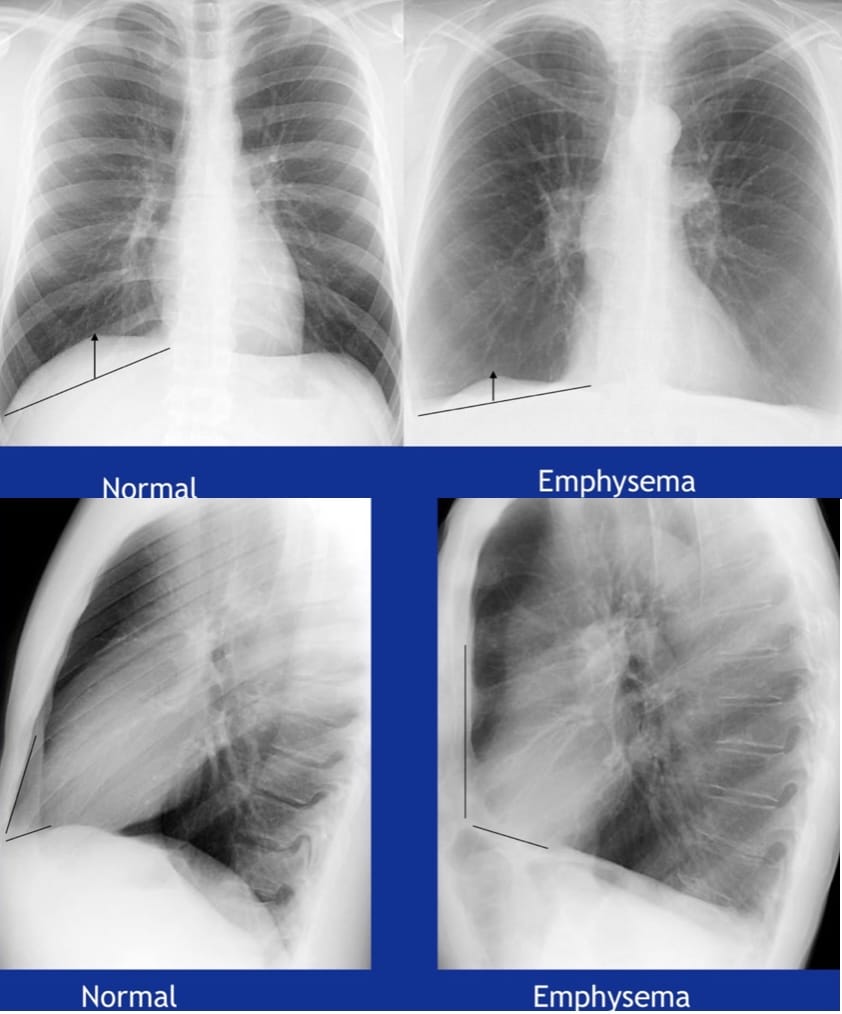

Emphysema

Destruction of alveolar walls and the permanent enlargement of the airspaces distal to the terminal bronchioles, without obvious fibrosis

Increased RV (a static lung volume) in COPD

We can make these distinctions on CT.

The effects on lung volumes correlate well with functional capacity and symptoms